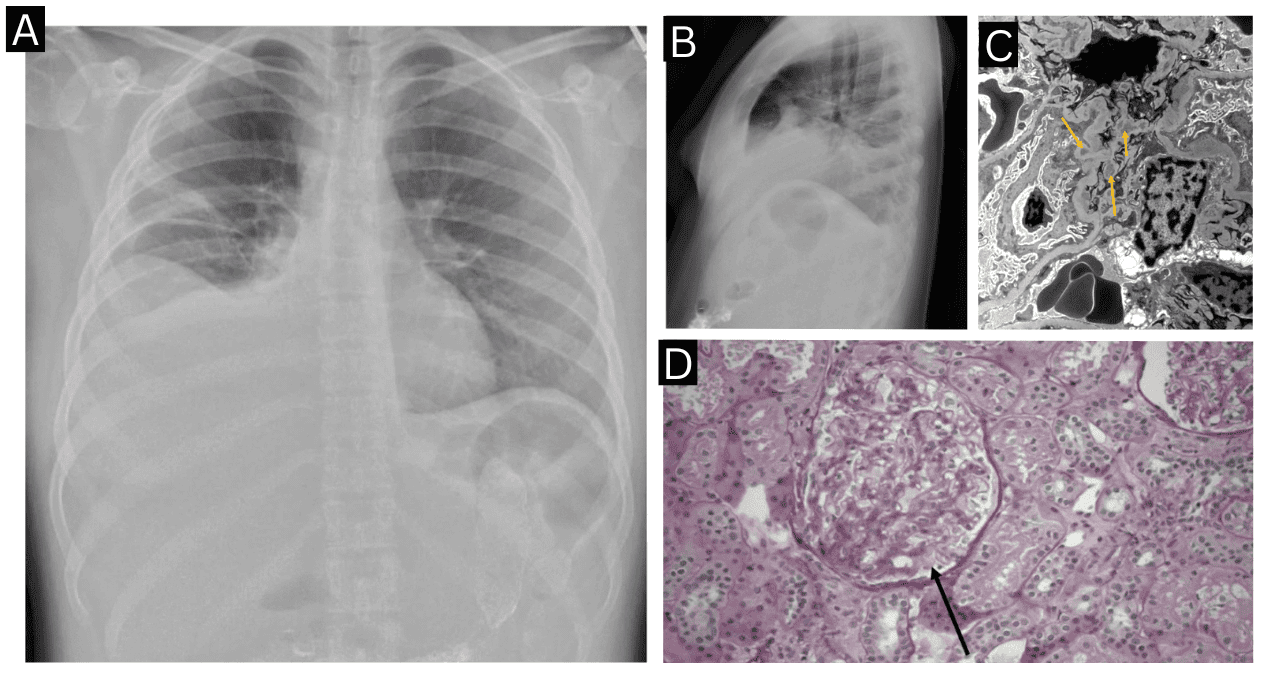

Ante estos hallazgos, se realizó biopsia renal que demostró nefritis lúpica proliferativa mesangial clase II, con microscopía electrónica mostrando depósitos mesangiales y eliminación difusa de podocitos.